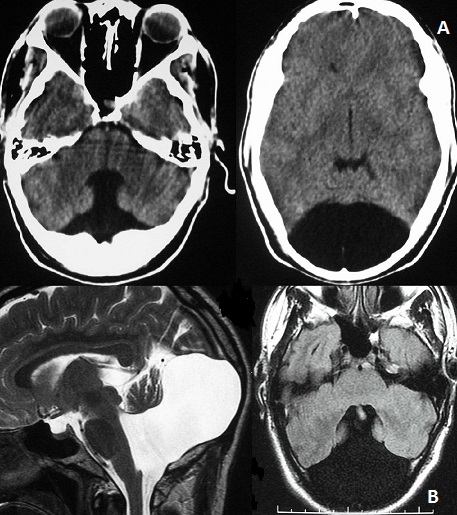

This 34 years old man presented with moderate and persistent headache occurring 48 hours following Benin head injury. There were no symptoms of increased intracranial pressure. Neurological examination was unremarkable without cerebellar ataxia or psychomotor retardation .the patient was submitted to CT scan and magnetic resonance imaging (MRI) of the brain that revealed agenesis of cerebellar vermis and large posterior fossa cyst communicating with the enlarged fourth ventricle suggestive of Dandy-Walker malformation without hydrocephalus. He was managed conservatively and he is doing well following 2 years ago. The Dandy-Walker syndrome (DWS) is a rare posterior fossa malformation and more rarely observed in adults. This case is unique in that the patient has been entirely asymptomatic with this abnormality since birth. The preserved cortical cytoarchitecture and the rarity of additional neurodevelopmental changes in DWS adults may explain the mild or absence of clinical expression, compared with DWS infants.